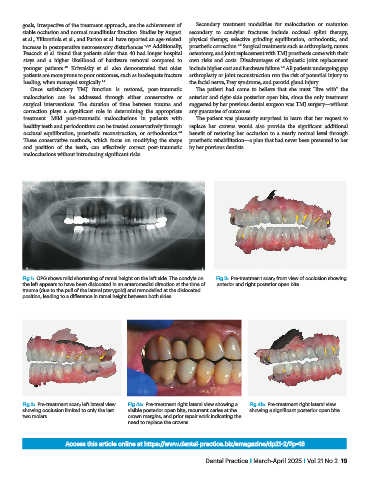

Fig 1: OPG shows mild shortening of ramal height on the left side. The condyle on Fig 2: Pre-treatment scan; front view of occlusion showing

the left appears to have been dislocated in an anteromedial direction at the time of anterior and right posterior open bite.

trauma (due to the pull of the lateral pterygoid) and remodelled at the dislocated

position, leading to a difference in ramal height between both sides.

Fig 3: Pre-treatment scan; left lateral view Fig 4a: Pre-treatment right lateral view showing a Fig 4b: Pre-treatment right lateral view

showing occlusion limited to only the last visible posterior open bite, recurrent caries at the showing a significant posterior open bite.

two molars. crown margins, and prior repair work indicating the

need to replace the crowns.